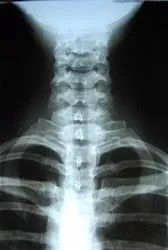

Digital radiography (digital x-ray) is the latest technology used to take upper cervical spine x-rays.This technique uses an electronic sensor (instead of x-ray film) that captures and stores the digital image on a computer. This image can be instantly viewed and enlarged helping the upper cervical chiropractor detect problems easier. Digital x-rays reduce radiation 80-90% compared to the already low exposure of traditional chiropractic x-rays.

Upper cervical spine x-rays are essential, preventative, diagnostic tools that provide valuable information, thus taking any guess work away by just examining your spine. Upper cervical chiropractors use this information to safely and accurately detect hidden spine abnormalities and complete an accurate treatment plan. Without x-rays, problem areas may go undetected.